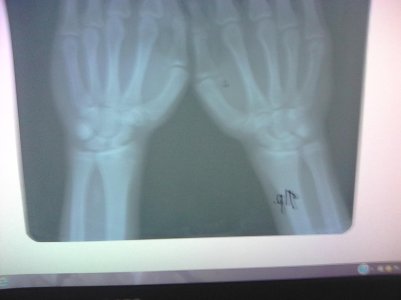

Здравствуйте. Скажите, пожалуйста, закрыты ли зоны роста на следующих снимках? Врач-эндокринолог сказала, что закрыты, но судя по прочитанным мною форумам врач может ошибаться. Врач-рентгенолог про зоны роста ничего не написала, только написала "костный возраст: 18-19 лет." Мне 18 лет, мой рост 161 см. Рост родителей: 152 см и 171 см. По направлению врача сдавал анализы на гормоны - всё в норме.